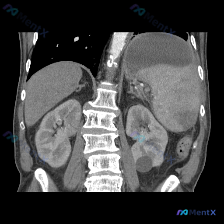

这是一张腹部CT冠状位重建(软组织窗):

- 最突出的异常:脾脏明显肿大,占据左上腹较大空间,下缘向下延伸,但脾实质密度看起来相对均匀

- 其他伴随发现:左肾下极有一类圆形低密度影,边缘锐利,符合单纯性肾囊肿表现;胃内有液平面提示积液/积气

- 关键阴性表现:肝脏右叶形态大致正常、边缘光滑,未见明显局灶性占位;未见明显腹腔大量积液;所见骨质结构大致正常